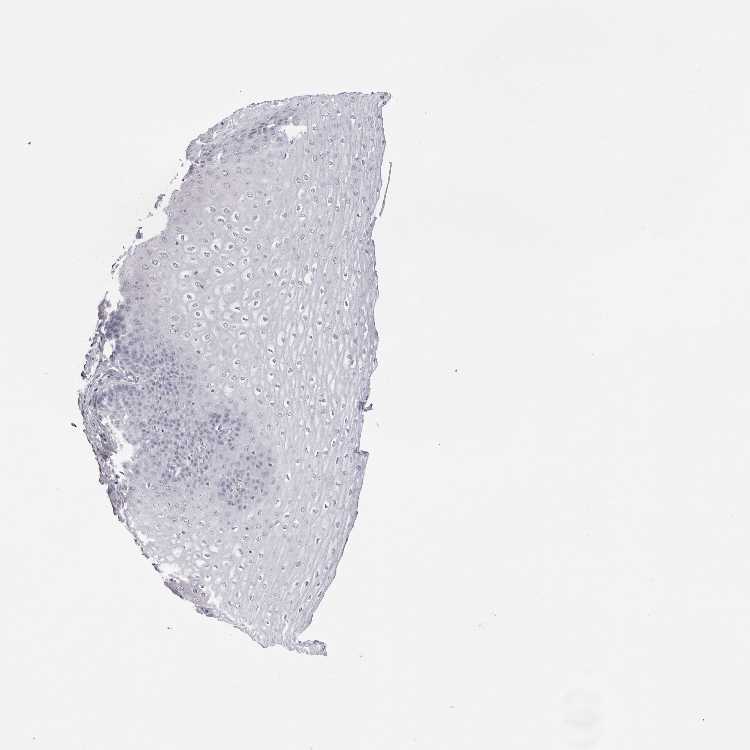

ESOPHAGUS - Antibody stainingi

Antibody staining in the annotated cell types in the current human tissue is reported as not detected, low, medium, or high, based on conventional immunohistochemistry profiling in selected tissues. This score is based on the combination of the staining intensity and fraction of stained cells.

Each image is clickable and will lead to virtual microscopy that enables deeper exploration of all samples and also displays staining intensity scores, fraction scores and subcellular localization as well as patient and tissue information for each sample.

Antibody HPA028048Antibody HPA028253Antibody CAB016193Antibody CAB037246

Squamous epithelial cells Not detectedNot detectedNot detectedLow